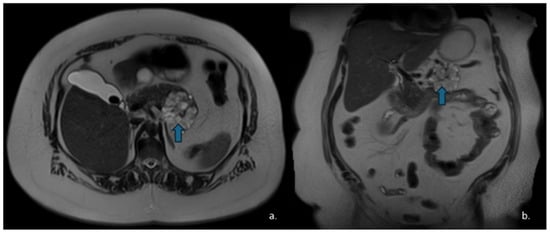

Figure 2.

Axial (a) and coronal (b) T2-weighted HASTE sequences show a hyperintense lesion (arrow) located at the head–body passage of the pancreas. The lesion is characterized by thin, hypointense internal septa. Endoscopic ultrasound revealed a microcystic serous cystadenoma.

Figure 4.

MRI of a 51-year-old woman. Coronal T2-w HASTE (a) and axial T2-w SPAIR (b) sequences show a hyperintense lesion (arrows) in the pancreatic head with a “cluster” morphology. Endoscopic ultrasound confirmed the diagnosis of a macrocystic serous cystadenoma.